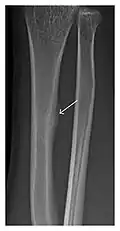

Fatigue fractures are more frequent in women which may be due to the relatively smaller bones of women. Moreover, pregnancy is a well-recognized risk factor for femoral neck fatigue fracture. While fibular and metatarsal fractures have a low risk of complications, other sites including the femoral neck, midanterior tibia, navicular, talar, and other intraarticular fractures are prone to complications such as delayed union, nonunion, and displacement. The site of the insufficiency fracture may be specific to the activity: for example, rugby and basketball players are more prone to navicular fractures, while gymnasts have a higher risk for talar fractures (Figure 7). Long distance runners are at increased risk for pelvic, tibial (Figures 8 and 9), and fibular fractures. In the military, calcaneus (Figure 10) and metatarsals are the most commonly cited injuries, especially in new recruits. Billiard players are at risk for upper limb fractures (Figure 11).[1]

Figure 11: Stress fracture of the right radius in a 40-year-old man, a semiprofessional billiard player, with no history of trauma and complaining of pain of the right forearm for one month. (a) Anteroposterior radiograph shows medial radial cortex periosteal reaction (arrow) but no fracture line is seen. (b) Coronal reformatted CT depicts monocortical fracture line through the periosteal thickening (arrowheads). (c) Coronal T2-weighted fat-suppressed MRI shows intramedullary hyperintensity within the bone marrow (arrow) corresponding to bone marrow edema.[1]